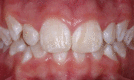

Purpose: To quantify the prevalence of white spot lesions (WSLs) on the anterior teeth and, secondarily, to evaluate risk factors and predictors.

Results: Overall, 23.4% of the patients developed at least one WSL during their course of treatment. Maxillary anterior teeth were affected more than mandibular teeth. The maxillary laterals and canines and the mandibular canines were the most susceptible. There was no significant difference in WSLs between genders. Fluorosis, treatment time in excess of 36 months, poor pretreatment hygiene, hygiene changes during treatment, and preexisting WSLs were all significantly (P < .05) related to the development of WSLs. The highest risk of developing WSLs was associated with preexisting WSLs (RR = 3.40), followed by declines in oral hygiene during treatment (RR = 3.12) and poor pretreatment oral hygiene (RR = 2.83).

Conclusions: Nearly 25% of the patients developed WSLs while in treatment, depending on fluorosis, treatment time, preexisting WSLs, and oral hygiene. Orthodontists need to be mindful of these risk factors when making treatment decisions.